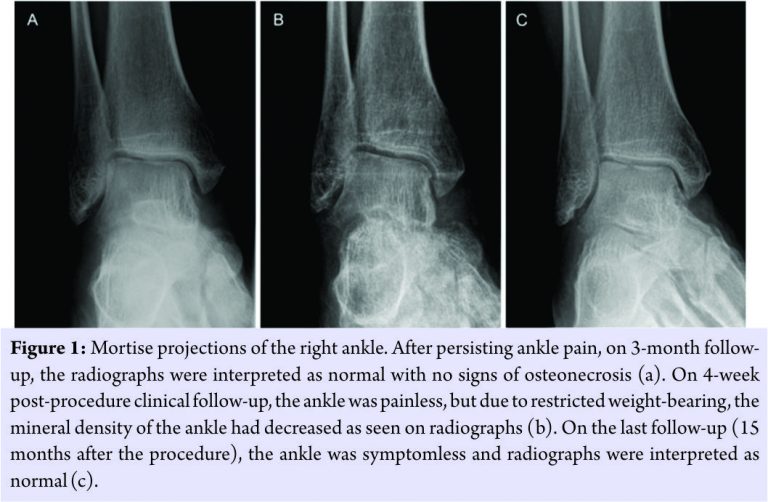

The radiographs were normal (Fig. 1a),but the MRI revealed ARCO Stage I osteonecrosis of the talus with increased signal on T2-weighted fat-saturated images and decreased signal on T1-weighted images; an additional minor crescent sign was also present (Fig. 2a and b). Due to the persisting pain and poor strain tolerance, core decompression with stem cell and PRP injection was performed using GPS® III (Gravitational Platelet Separation System; Zimmer-Biomet, Warsaw, Indiana, USA) and BioCUE BMA (Bone Marrow Aspirate [BMA] Concentration System; Zimmer-Biomet, Warsaw, Indiana, USA) systems. First, 30 ml of venous blood (including 3 ml of anticoagulant) was collected from the patient and centrifuged for 15 min. Accordingly, 3 ml of PRP was recovered from the centrifuged sample. In operating room under general anesthesia, autologous aspiration of bone marrow-derived stem cells from the right anterior iliac crest was carried out by an orthopedic surgeon. In total, 60 ml of BMA was collected and subsequently centrifuged for 15 min producing 6 ml of concentrated BMA. Finally, the PRP and BMA were mixed producing a total of 9 ml of the injectate. A stab incision on the anteroinferior edge of the medial malleolus was performed, and on fluoroscopic control, a guidance spike was directed into the talus to the region of the osteonecrosis.

A 2.7 mm cannulated drill was used to provide core decompression. Routine histopathological specimens were not produced due to typical findings of osteonecrosis on MRI. Next, the PRP-BMA concoction was injected into the osteonecrotic region under fluoroscopic control using a 3 mm aspiration needle (Fig. 3). The incision wound was closed and full weight-bearing was restricted for 4 weeks with free mobilization of the ankle. On 4-week clinical follow-up, the patient presented no pain in the right ankle. Radiographs were normal except for the low mineral density of the bones in general (Fig. 1b). On the 3-month follow-up, the patient had fully resumed to his daily activities and his ankle was symptomless. The MRI revealed virtually complete resolution of the talar osteonecrotic changes (Fig. 2c and d). On the subsequent 15-month follow-up, the patient presented no symptoms and the MRI scan (Fig. 2e and f) as well as the radiographs (Fig. 1c) were normal.